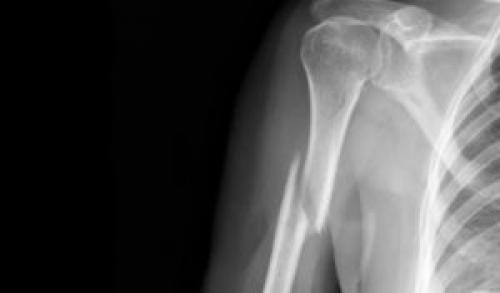

Консервативная терапия

Простые переломы без смещений либо с незначительными сдвигами отломков подлежат одномоментной репозиции. Следующий этап — фиксация поврежденного плеча специальными накладками, гипсовой повязкой. Чаще всего обеспечивается неподвижность участка от лопатки до предплечья с фиксацией трёх суставов. Лечение вколоченного перелома предусматривает крепление отводящих подушек или специальных косынок.

Срок иммобилизации зависит от тяжести перелома, составляет 30−60 дней. Наличие сильного отека кисти, синюшности на пальцах — признак осложнения, гипсовую повязку нужно снять или развести края, чтобы ослабить гипс. Повреждение костных структур часто влечет за собой травмы сосудов, нервов. В таких случаях требуется оперативное лечение, что, в целом, увеличивает срок общей терапии.

Гипсовая иммобилизация плечевой кости при переломе

Здравствуйте. Гипс накладывают в зависимости от вида перелома (открытого и закрытого) и места травмы: на проксимальном конце плечевой кости, диафизе или дистальном конце. Кроме этого перелом может быть внесуставным (с изолированным повреждением малого и большого бугорка, хирургической шейки), а также внутрисуставным: повреждается головка и анатомическая шейка проксимального конца кости плеча.

Другой вариант наложения гипса на плечевую кость